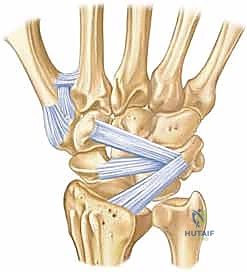

يتكون الرسغ من ثماني عظام صغيرة تُعرف بعظام الرسغ (Carpal bones)، مرتبة في صفين (صف قريب وصف بعيد). بينما يستحوذ العظم الزورقي (Scaphoid) على النصيب الأكبر من الكسور والاهتمام الطبي، فإن العظام السبعة الأخرى تلعب أدواراً حاسمة لا تقل أهمية.

العظام غير الزورقية وأهميتها:

- العظم الهلالي (Lunate): يقع في منتصف الصف القريب، وهو حجر الزاوية في حركة الرسغ. كسوره نادرة ولكنها خطيرة جداً وقد تؤدي إلى انقطاع التروية الدموية (مرض كينبوك).

- العظم المثلثي (Triquetrum): ثاني أكثر عظام الرسغ عرضة للكسر بعد الزورقي. غالباً ما تحدث كسوره نتيجة السقوط على يد ممتدة.

- العظم الحمصي (Pisiform): عظمة صغيرة تعمل كبكرة للأوتار. كسورها تؤثر على قوة القبضة.

- العظم المربعي (Trapezium): يتمفصل مع إبهام اليد، وكسوره تؤثر بشدة على حركة الإبهام والقدرة على الإمساك بالأشياء.

- العظم شبه المنحرف (Trapezoid): عظمة محمية جداً، وكسورها نادرة للغاية، وتحدث غالباً بسبب صدمات عنيفة جداً.

- العظم الكبير (Capitate): أكبر عظام الرسغ ويقع في المركز. كسوره تتطلب قوة كبيرة وتترافق غالباً مع إصابات أخرى.

- العظم الكلابي (Hamate): يمتلك بروزاً عظمياً يُسمى "الخطاف". كسور هذا الخطاف شائعة بين الرياضيين (لاعبي التنس، الجولف، البيسبول) وتسبب ألماً مزمناً إذا لم تُشخص.